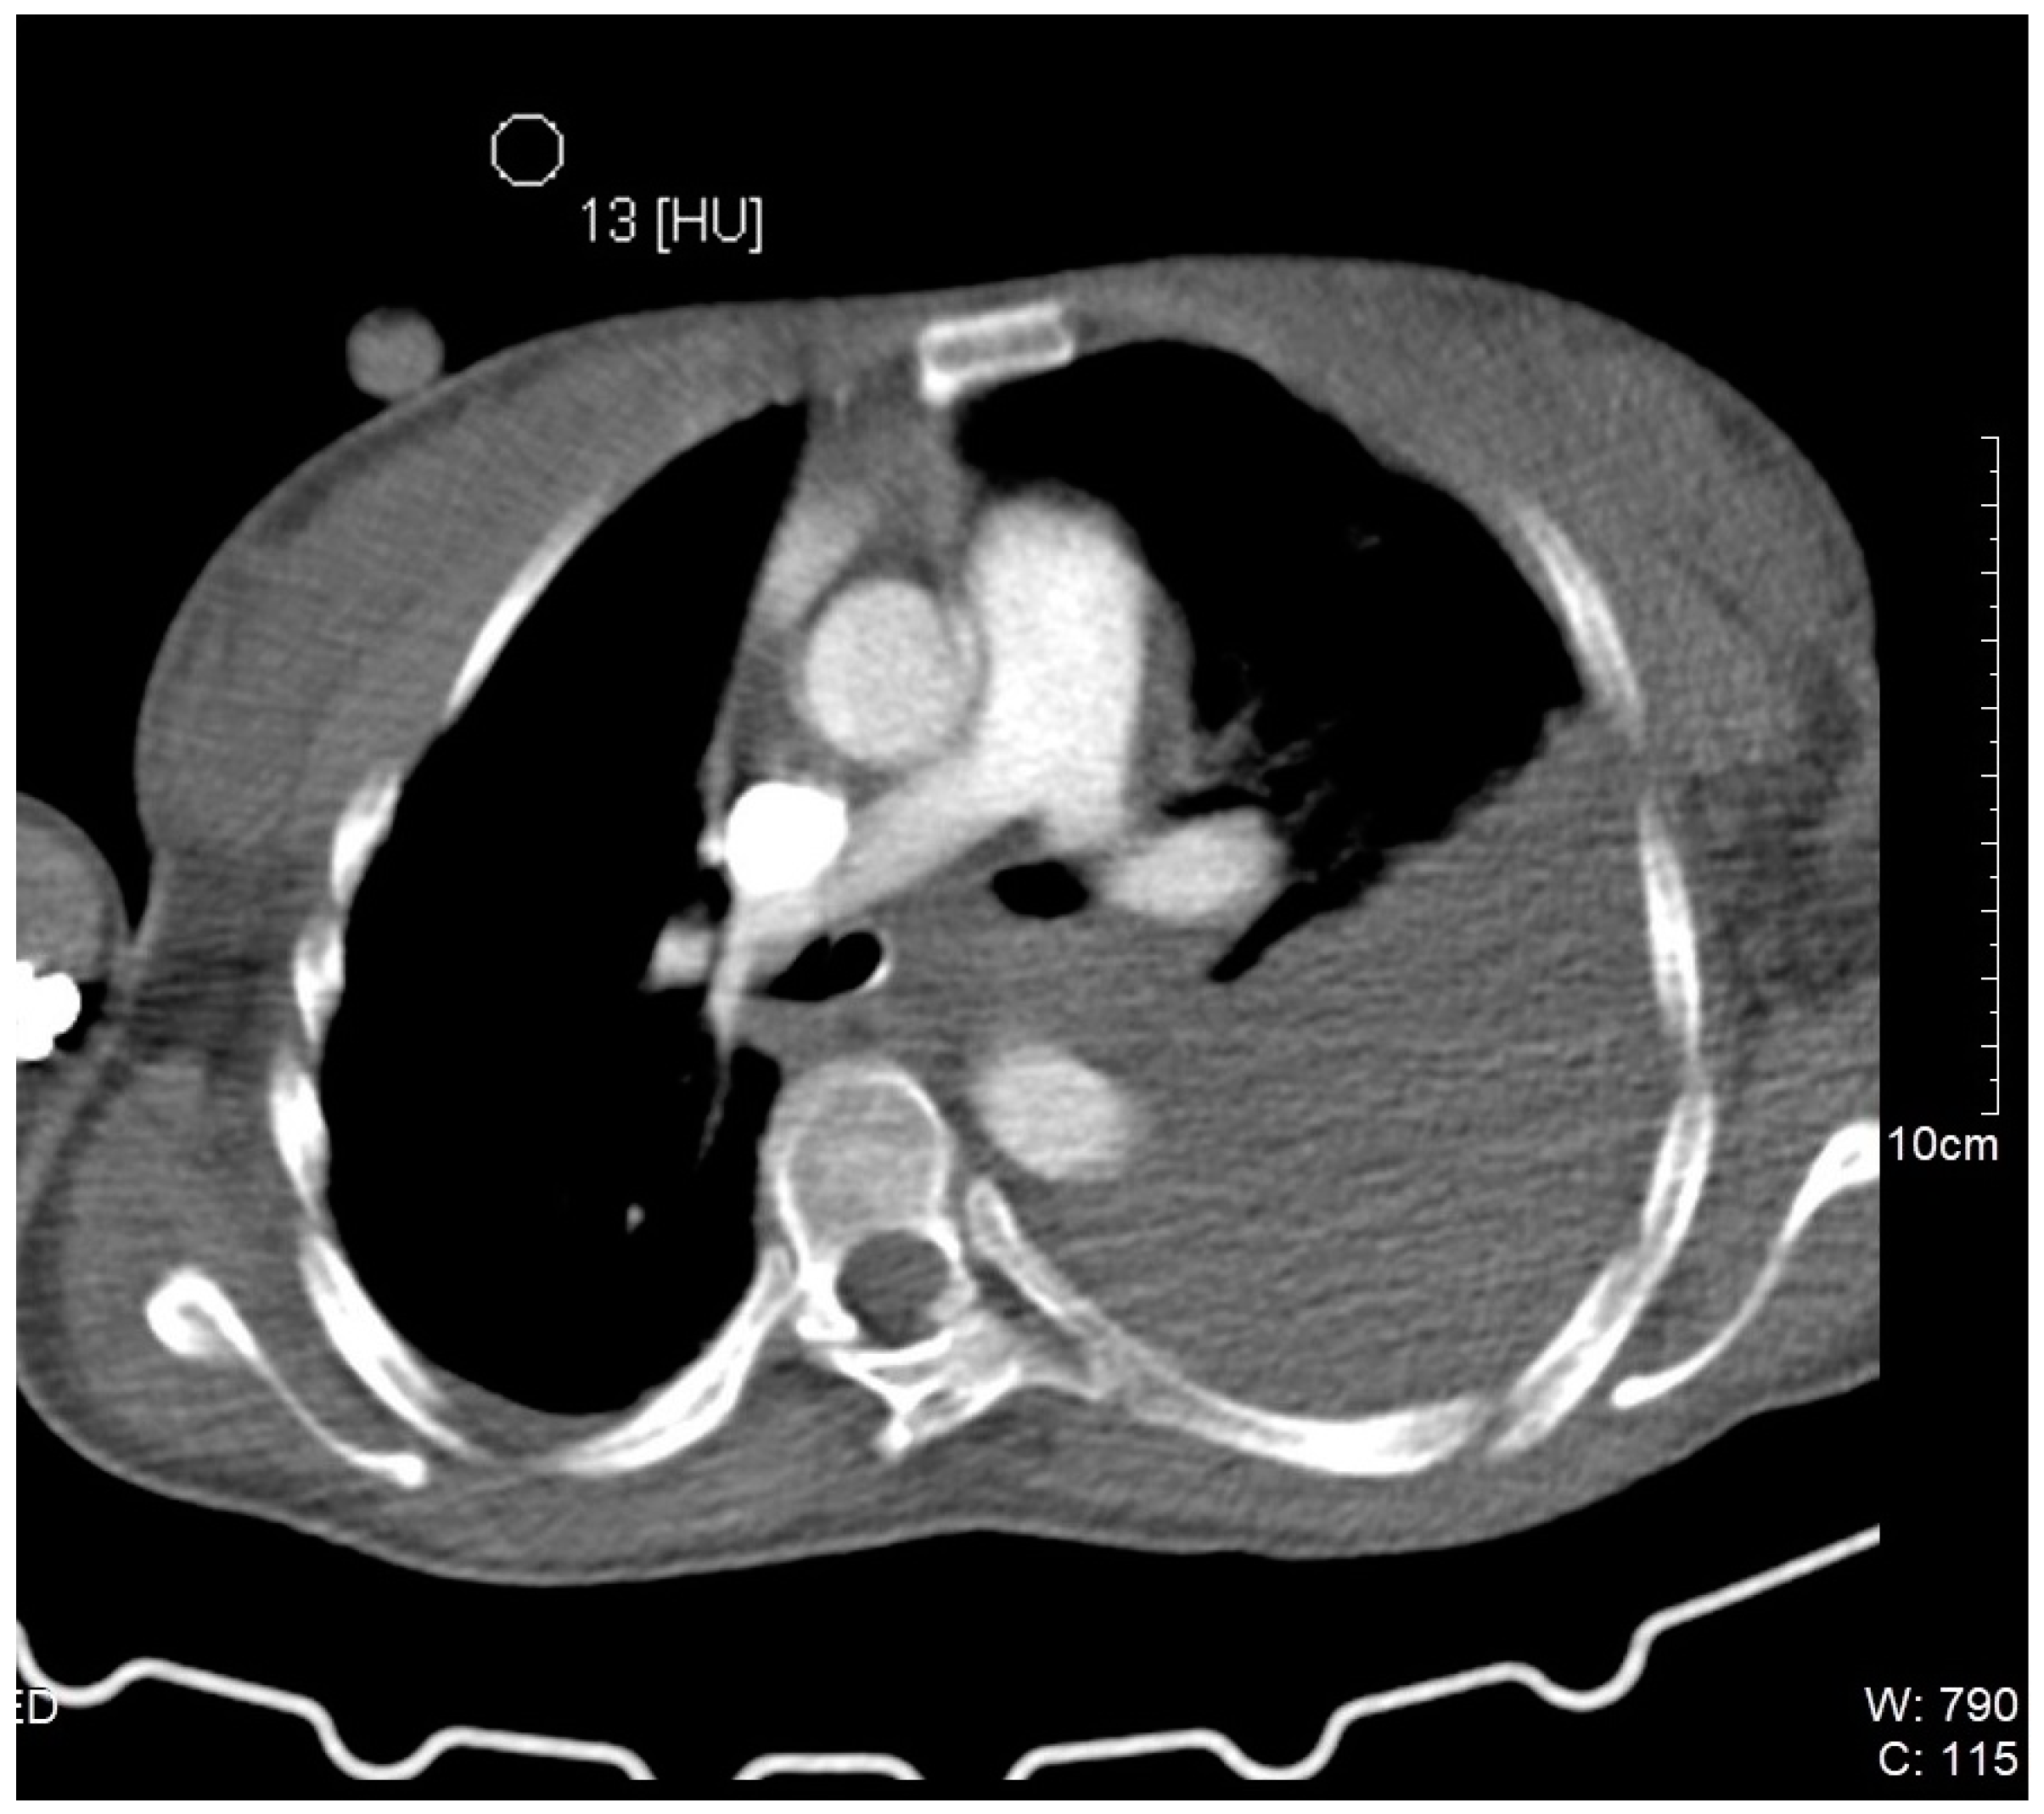

Successful Management of Thyrocervical Trunk Aneurysm Ruptured into the Thoracic Cavity After Cesarean Section in Nonstable Patient with Neurofibromatosis Type I

2. Case Description